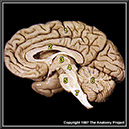

N2A3P1

38